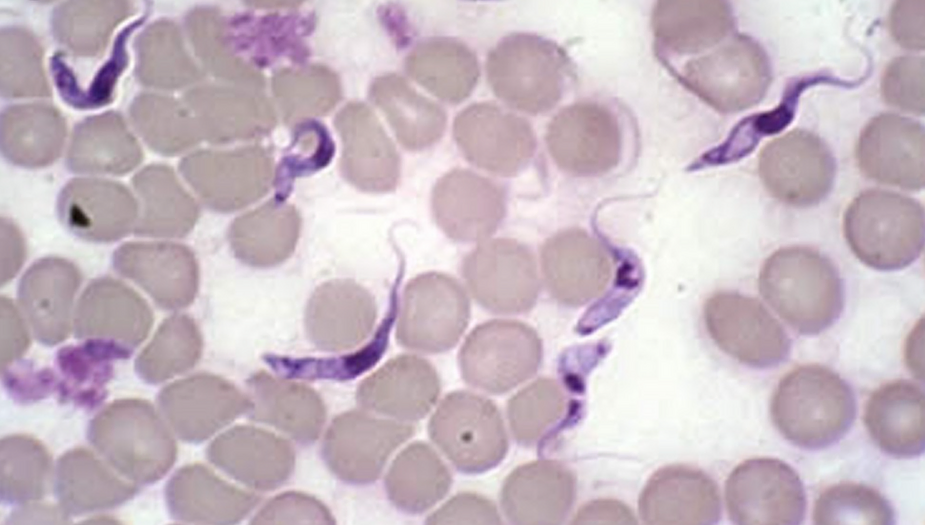

As the UK statics are showing now, the majority dying from the Vax are those that have been triple injected with the gene altering graphene, ferritin, luciferase, PEG and parasitical toxic with the Trypanosoma parasite causing myocardititis all in the so-called CoVid – 19 vaccine serum.